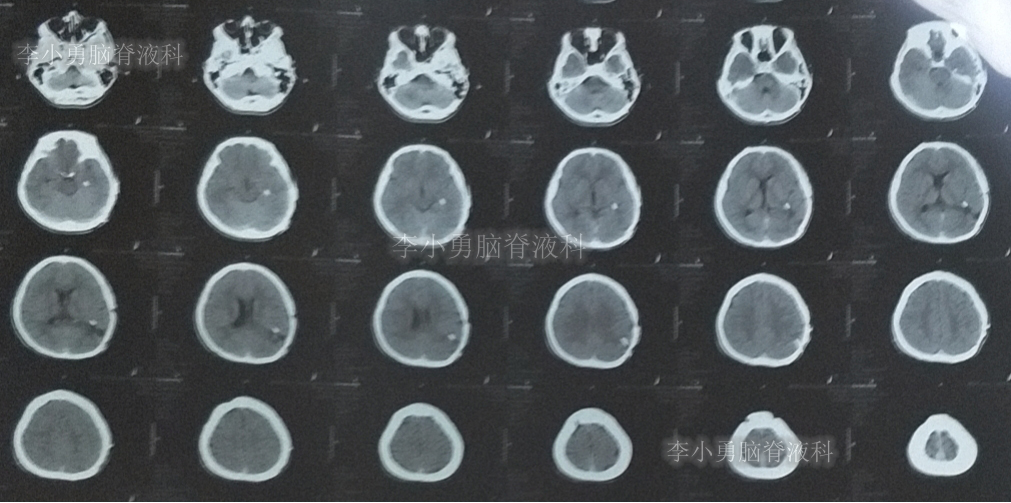

双侧脑室外引流5天后即2019年3月31日,脑脊液颜色由血性明显变淡,意识转清,肢体活动良好,给予复查头颅CT(图-3):脑室不大,残留少许积血。

图-3:2019年3月31日头颅CT:残留少许积血

次日即2019年4月2日给予行腰椎穿刺术,引流出血性脑脊液;但腰椎穿刺术刚结束突然晕厥,再次复查头颅CT(图-4):脑室内出血量较前明显增多,四脑室及中央导水管铸形。

图-4:2019年4月2日头颅CT:脑室内积血明显增多

次日2019年4月3日(脑出血后8天),转至河南省郑州市某三甲医院;入院当日头颅CT(图-5)及CTA(图-6)检查结果:出血量较昨日无增加,动脉血管未见明显异常。

图-5:2019年4月3日头颅CT:出血量无增加